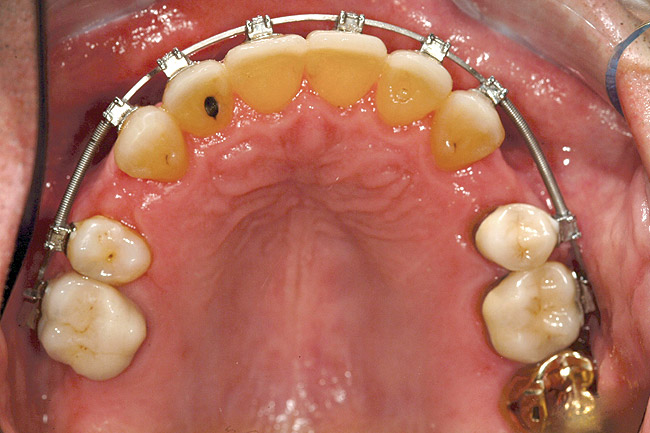

Fig 4. Note gingival inflammation caused by biologic width violation. Provisional restorations were placed on Nos. 6, 8, 9, and 11, and corticotomies were performed from Nos. 3 to 14.

Figure 4

Fig 5. One week postsurgery with mesial buildups on Nos. 5 and 12 and thin pontics on archwire to conceal spaces during closure.

Figure 5